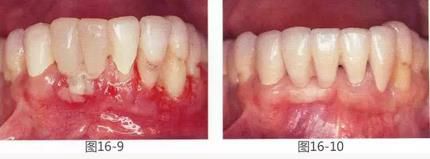

360截圖20170422142104852.jpg

圖18-1  右下磨牙區(qū)牙槽嵴在頰舌側(cè)存在嚴(yán)重的吸收。

圖18-2  同部斷面的X光片。銳利尖角的牙槽嵴形態(tài)。